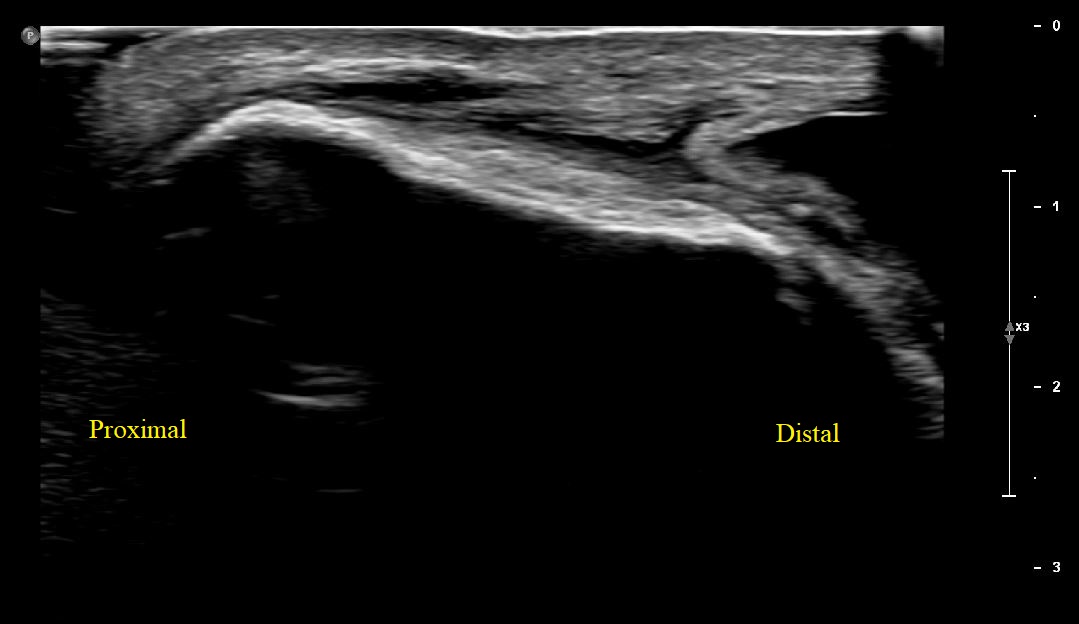

Short Axis view of Right proximal patellar tendon showing large complex fluid within the prepatellar bursa with bursal lining hypertrophy at the base.

Long Axis view of Right Proximal Patellar tendon with large complex fluid within the prepatellar bursa with bursal lining hypertrophy. Patellar tendon is intact.

Long Axis view of Right Proximal Patellar tendon with overlying prepatellar bursal distension